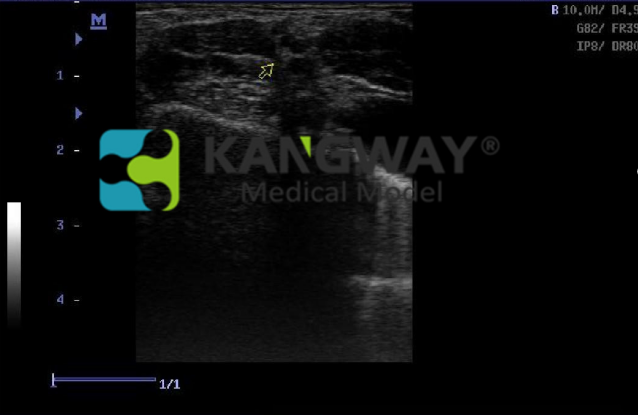

為培訓超聲引導下而專門設(shè)計的。適用于診斷超聲影像科的教學與培訓。培訓超聲引導下的周圍神經(jīng)阻滯局部麻醉操作手法以及動靜脈置管手法,可供醫(yī)生實踐并反復練習把握使用超聲引導區(qū)域麻醉和血管通路程序所必需的技能。

3.由仿生人體硅膠制成,真實的人體組織觸感,且該材料與人體組織擁有相同的聲學特性,超聲圖像極為真實,且堅固耐用,可大大減少損耗,節(jié)約成本;

4. 包含根直徑為2mm的神經(jīng)支和二根直徑為1mm的神經(jīng)支

9.可與市面上任何超聲設(shè)備結(jié)合完成超聲影像訓練與考核。